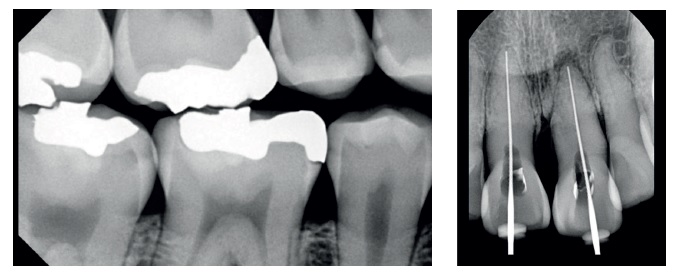

I sensori EzSensor Slim offrono un elevato potere di restituzione di tutta la gamma tonale.

Comparando la gamma dinamica di tonalità si nota come in molti sensori concorrenti ci siano aree in cui la differenza tonale è troppo scarsa.

Ciò non permette di distinguere dettagli quando il contrasto tra le tessuti e strutture è troppo lieve.

Sfruttando l’elevata gamma dinamica del sensore anche ridotte esposizioni sono sufficienti per condurre esami approfonditi e ottenere immagini di ottima qualità.

In questo modo i pazienti sono salvaguardati dall’eccesso di radiazioni.